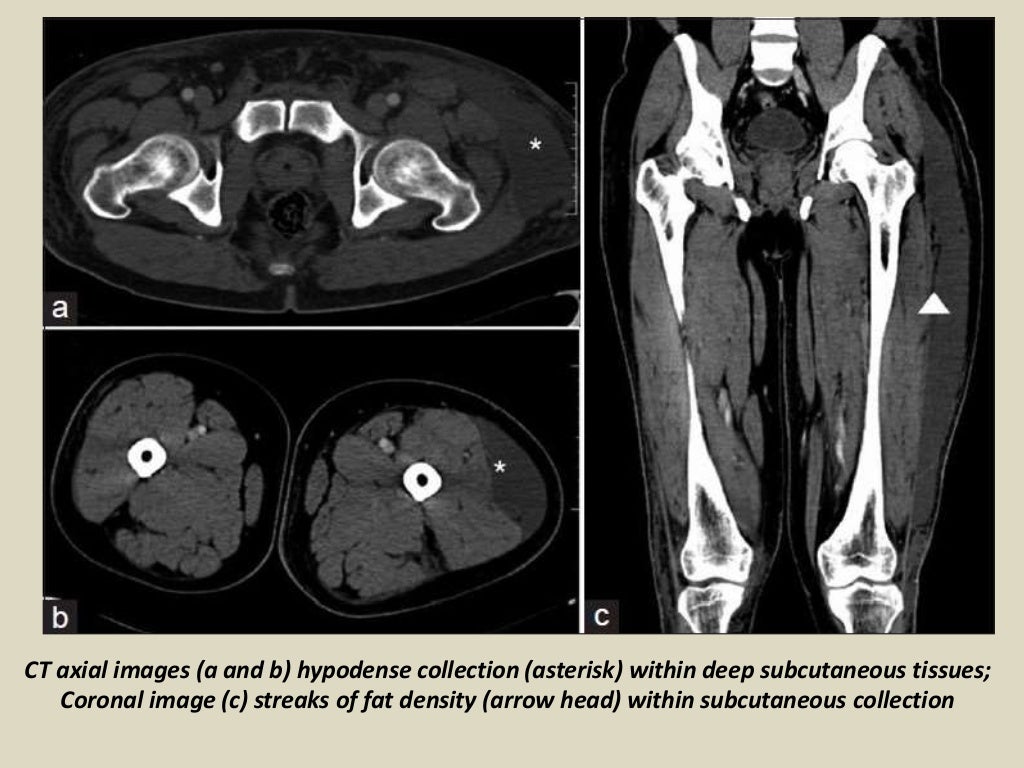

Presentation1, radiological imaging of morel lavallee lesion. Morel Lavallee Lesion Ppt 1 the injury is characterized by the separation of the hypodermis from the underlying fascia and. Submit your diagnosis to see full. An ml lesion is characterized by a traumatic separation of the dermis from the adjacent fascia layer. The lymphatic and vascular structures are. Morel Lavallee Lesion Ppt.

Presentation1, radiological imaging of morel lavallee lesion. Morel Lavallee Lesion Ppt An ml lesion is characterized by a traumatic separation of the dermis from the adjacent fascia layer. The lymphatic and vascular structures are. 1 the injury is characterized by the separation of the hypodermis from the underlying fascia and. Submit your diagnosis to see full. Morel Lavallee Lesion Ppt.

Presentation1, radiological imaging of morel lavallee lesion. Morel Lavallee Lesion Ppt The lymphatic and vascular structures are. Submit your diagnosis to see full. 1 the injury is characterized by the separation of the hypodermis from the underlying fascia and. An ml lesion is characterized by a traumatic separation of the dermis from the adjacent fascia layer. Morel Lavallee Lesion Ppt.

Presentation1, radiological imaging of morel lavallee lesion. Morel Lavallee Lesion Ppt The lymphatic and vascular structures are. Submit your diagnosis to see full. An ml lesion is characterized by a traumatic separation of the dermis from the adjacent fascia layer. 1 the injury is characterized by the separation of the hypodermis from the underlying fascia and. Morel Lavallee Lesion Ppt.

Presentation1, radiological imaging of morel lavallee lesion. Morel Lavallee Lesion Ppt Submit your diagnosis to see full. 1 the injury is characterized by the separation of the hypodermis from the underlying fascia and. An ml lesion is characterized by a traumatic separation of the dermis from the adjacent fascia layer. The lymphatic and vascular structures are. Morel Lavallee Lesion Ppt.

Presentation1, radiological imaging of morel lavallee lesion. Morel Lavallee Lesion Ppt 1 the injury is characterized by the separation of the hypodermis from the underlying fascia and. Submit your diagnosis to see full. The lymphatic and vascular structures are. An ml lesion is characterized by a traumatic separation of the dermis from the adjacent fascia layer. Morel Lavallee Lesion Ppt.

Presentation1, radiological imaging of morel lavallee lesion. Morel Lavallee Lesion Ppt 1 the injury is characterized by the separation of the hypodermis from the underlying fascia and. An ml lesion is characterized by a traumatic separation of the dermis from the adjacent fascia layer. Submit your diagnosis to see full. The lymphatic and vascular structures are. Morel Lavallee Lesion Ppt.